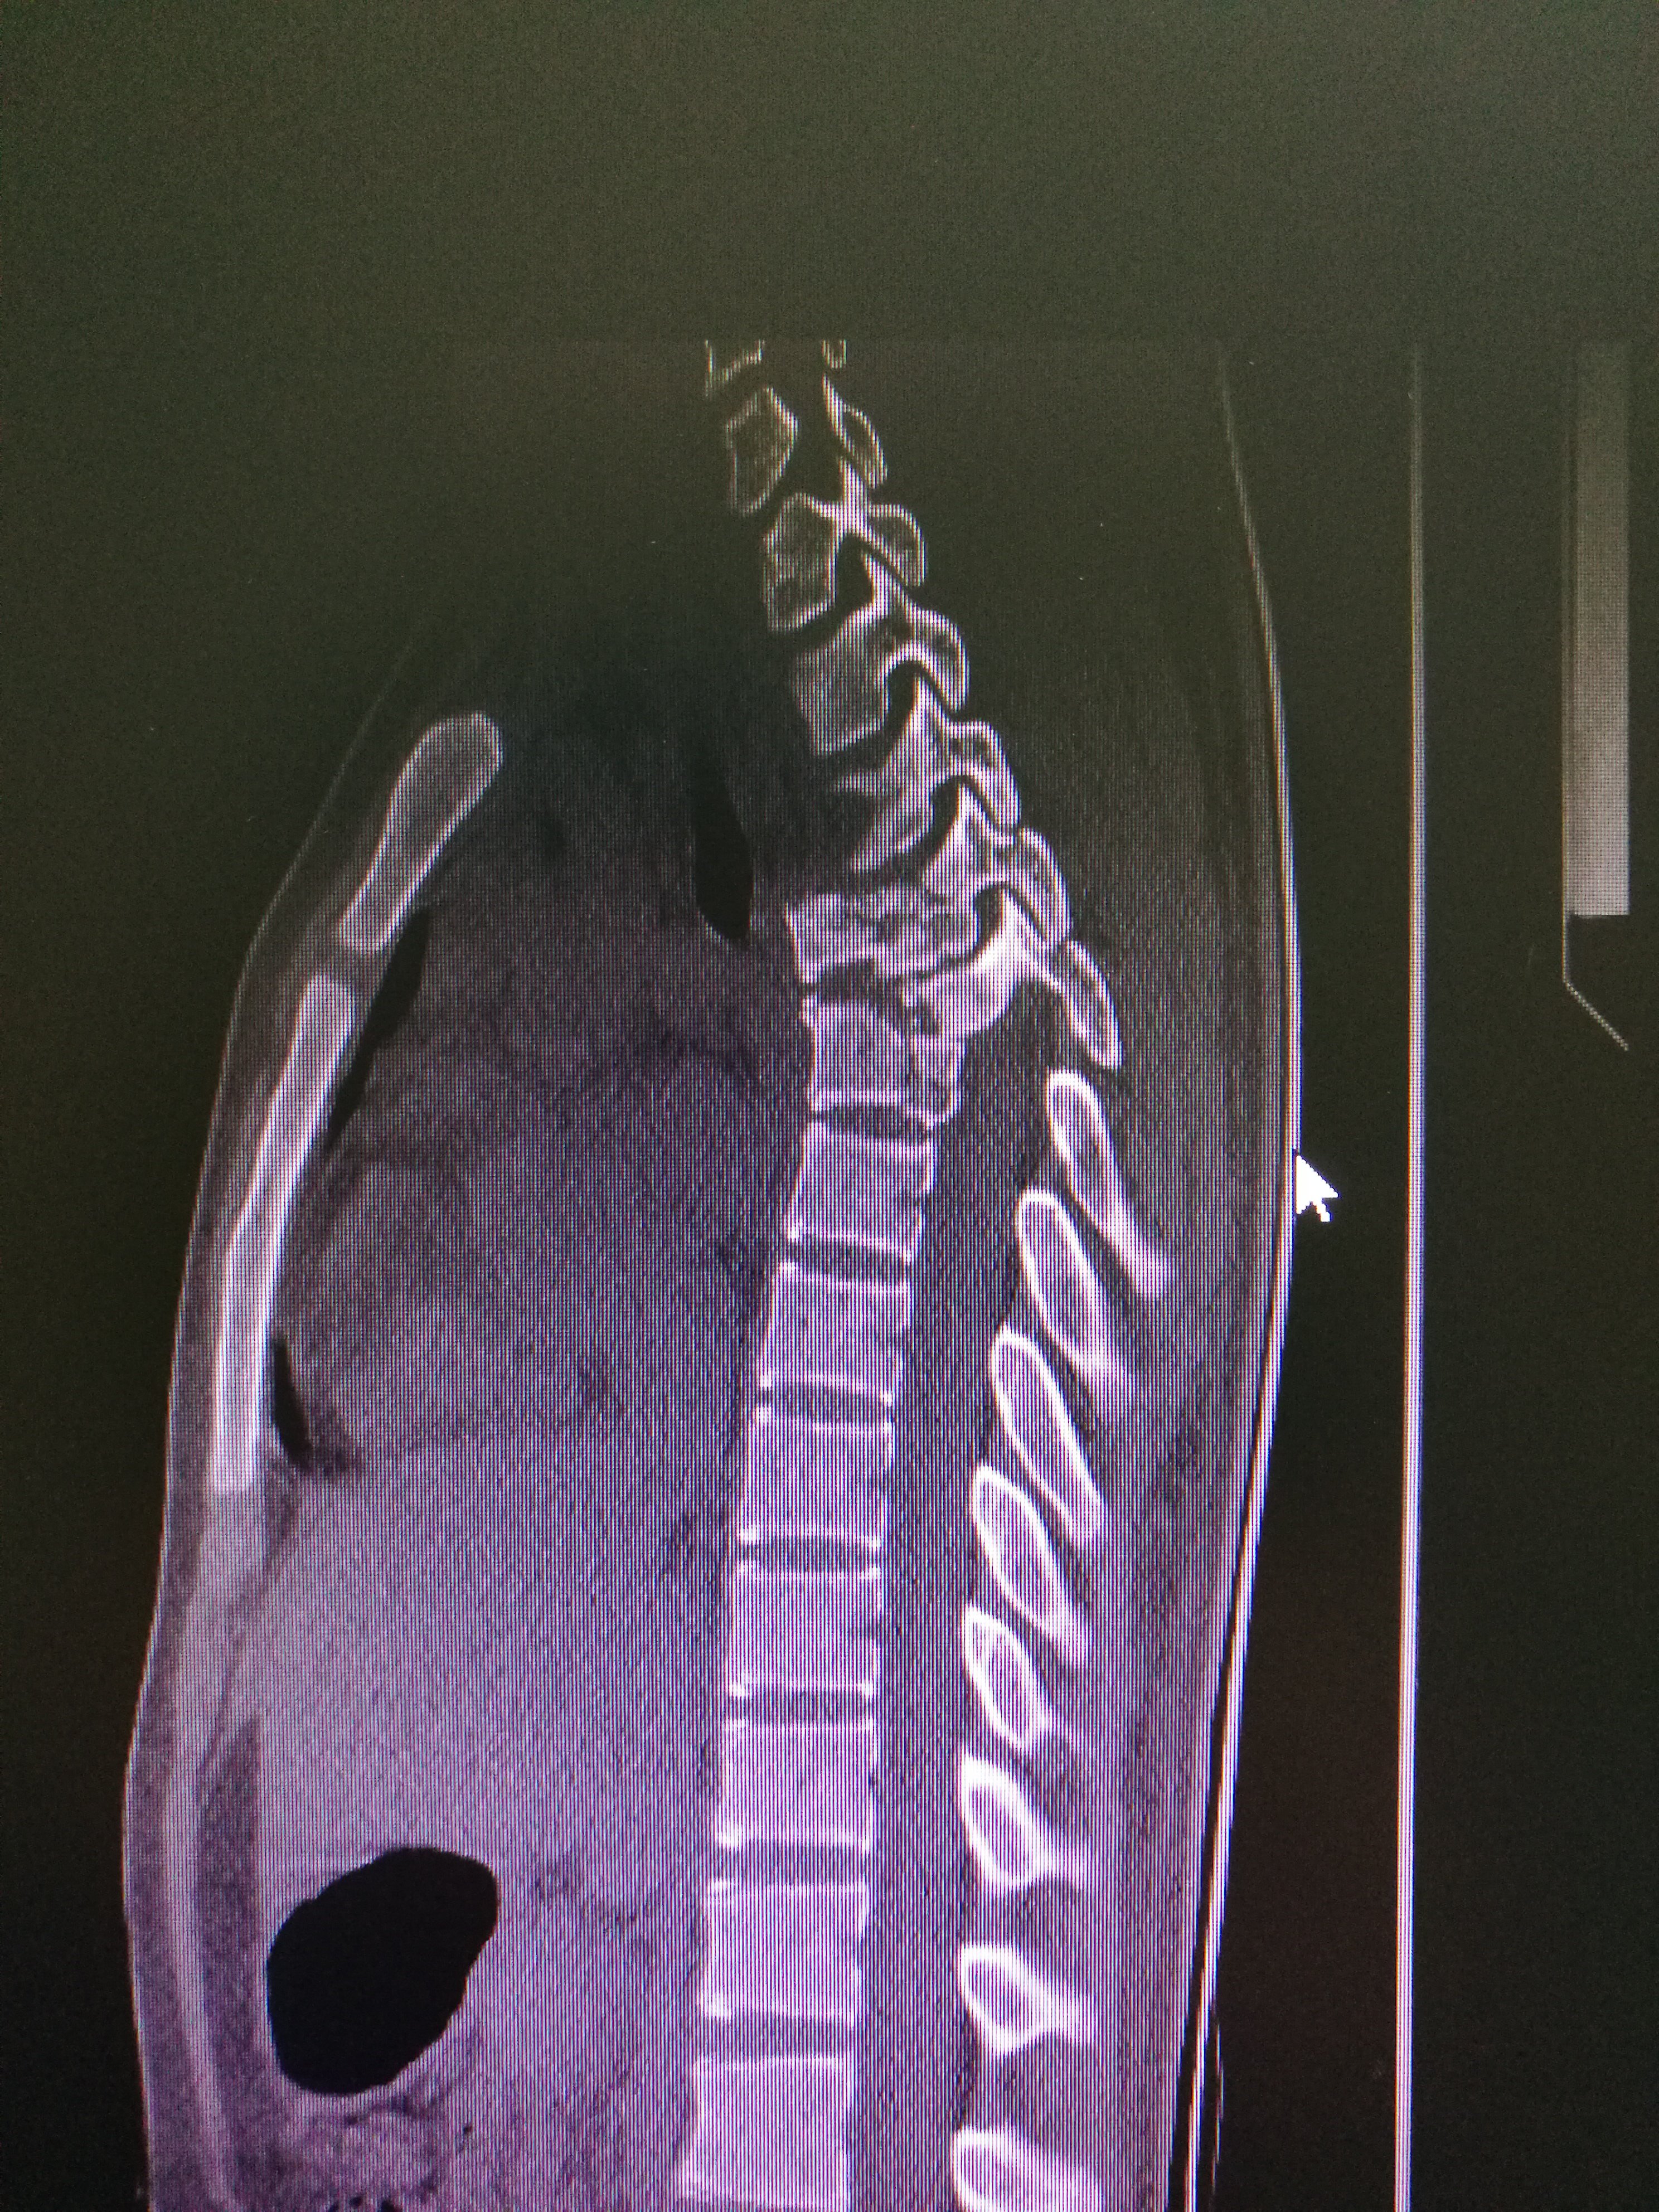

一期后路三柱重建治疗严重胸椎爆裂骨折

磁共振显示胸椎骨折,脊髓严重受压